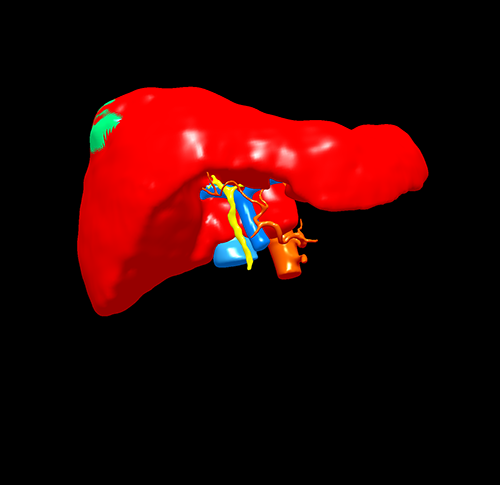

右肝肿瘤----腹腔镜右半肝切除